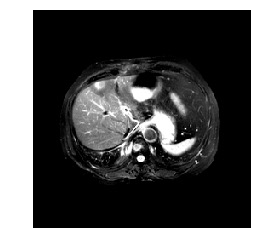

Medical image segmentation methods normally perform poorly when there is a domain shift between training and testing data. Unsupervised Domain Adaptation (UDA) addresses the domain shift problem by training the model using both labeled data from the source domain and unlabeled data from the target domain. Source-Free UDA (SFUDA) was recently proposed for UDA without requiring the source data during the adaptation, due to data privacy or data transmission issues, which normally adapts the pre-trained deep model in the testing stage. However, in real clinical scenarios of medical image segmentation, the trained model is normally frozen in the testing stage. In this paper, we propose Fourier Visual Prompting (FVP) for SFUDA of medical image segmentation. Inspired by prompting learning in natural language processing, FVP steers the frozen pre-trained model to perform well in the target domain by adding a visual prompt to the input target data. In FVP, the visual prompt is parameterized using only a small amount of low-frequency learnable parameters in the input frequency space, and is learned by minimizing the segmentation loss between the predicted segmentation of the prompted target image and reliable pseudo segmentation label of the target image under the frozen model. To our knowledge, FVP is the first work to apply visual prompts to SFUDA for medical image segmentation. The proposed FVP is validated using three public datasets, and experiments demonstrate that FVP yields better segmentation results, compared with various existing methods.